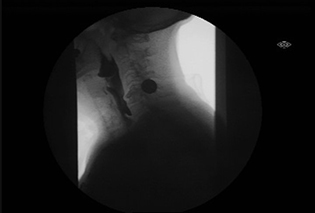

Zanker's Diverticulum Fluoro

Appearance of Zenker’s Diverticulum showing retention of contrast in cervical esophagus under fluoroscopy.